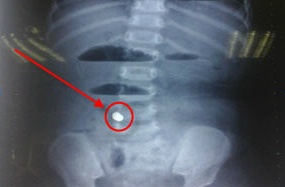

Bệnh nhân là cháu T. ( 30 tháng tuổi ), ở ấp 5, xã Vĩnh Lộc A, huyện Bình Chánh, TP.HCM. Ngày 25-7, cháu T. được đưa vào Bệnh viện Nhi Đồng 1 với triệu chứng bị ói, sốt, sau đó cháu bị tiêu...